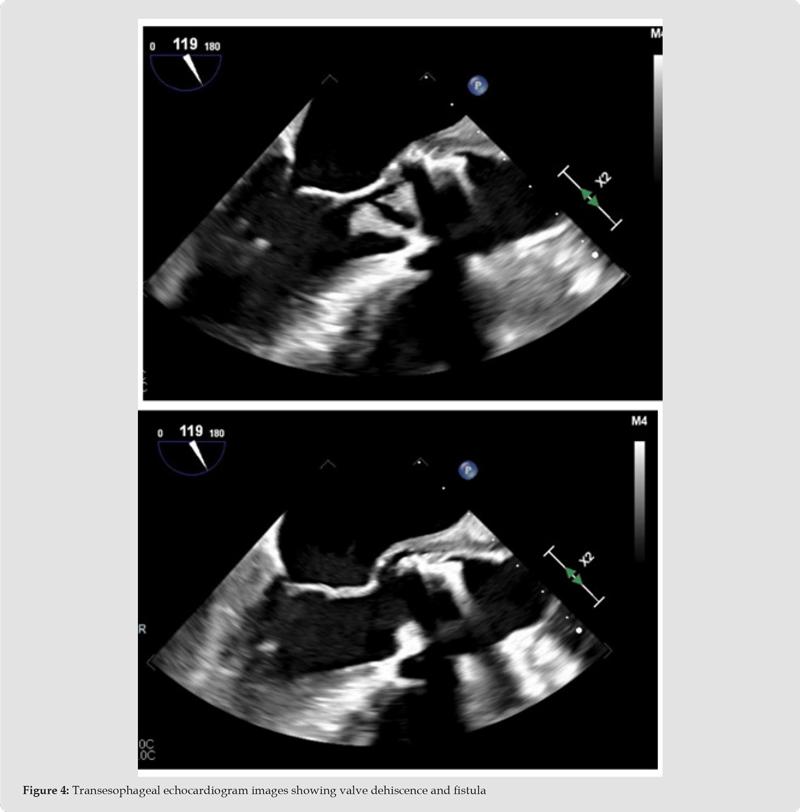

Subsequently, the patient underwent transesophageal echocardiography (TEE) which showed a large mobile echogenicity attached to the aortic valve bio-prosthesis, dehiscence along the aortic-mitral continuity and a thickened periaortic region. (Figure 4) Despite negative blood cultures up until that point, the findings were thought to be consistent with highly complicated endocarditis of the bioprosthetic aortic valve with fistula and periaortic abscess. TEE also showed moderate mitral and tricuspid regurgitation; there was no evidence of endocarditis involving the mitral, tricuspid or pulmonic valves. On day five of growth, both blood cultures grew C.hominis and hence a diagnosis of endocarditis complicated with paravalvular abscess was made. The patient was referred to quaternary center where she underwent redo-sternotomy with aortic valve and root replacement with a 24 mm aortic homograft, in addition to mitral and tricuspid valve repair. She received epicardial right atrial and right ventricular leads with generator placement without any significant complications [7]. As expected, surgical pathology of the valvular vegetation was consistent with bacterial endocarditis. The patient continued to do well in the immediate post-operative period and was successfully discharged home in stable condition.